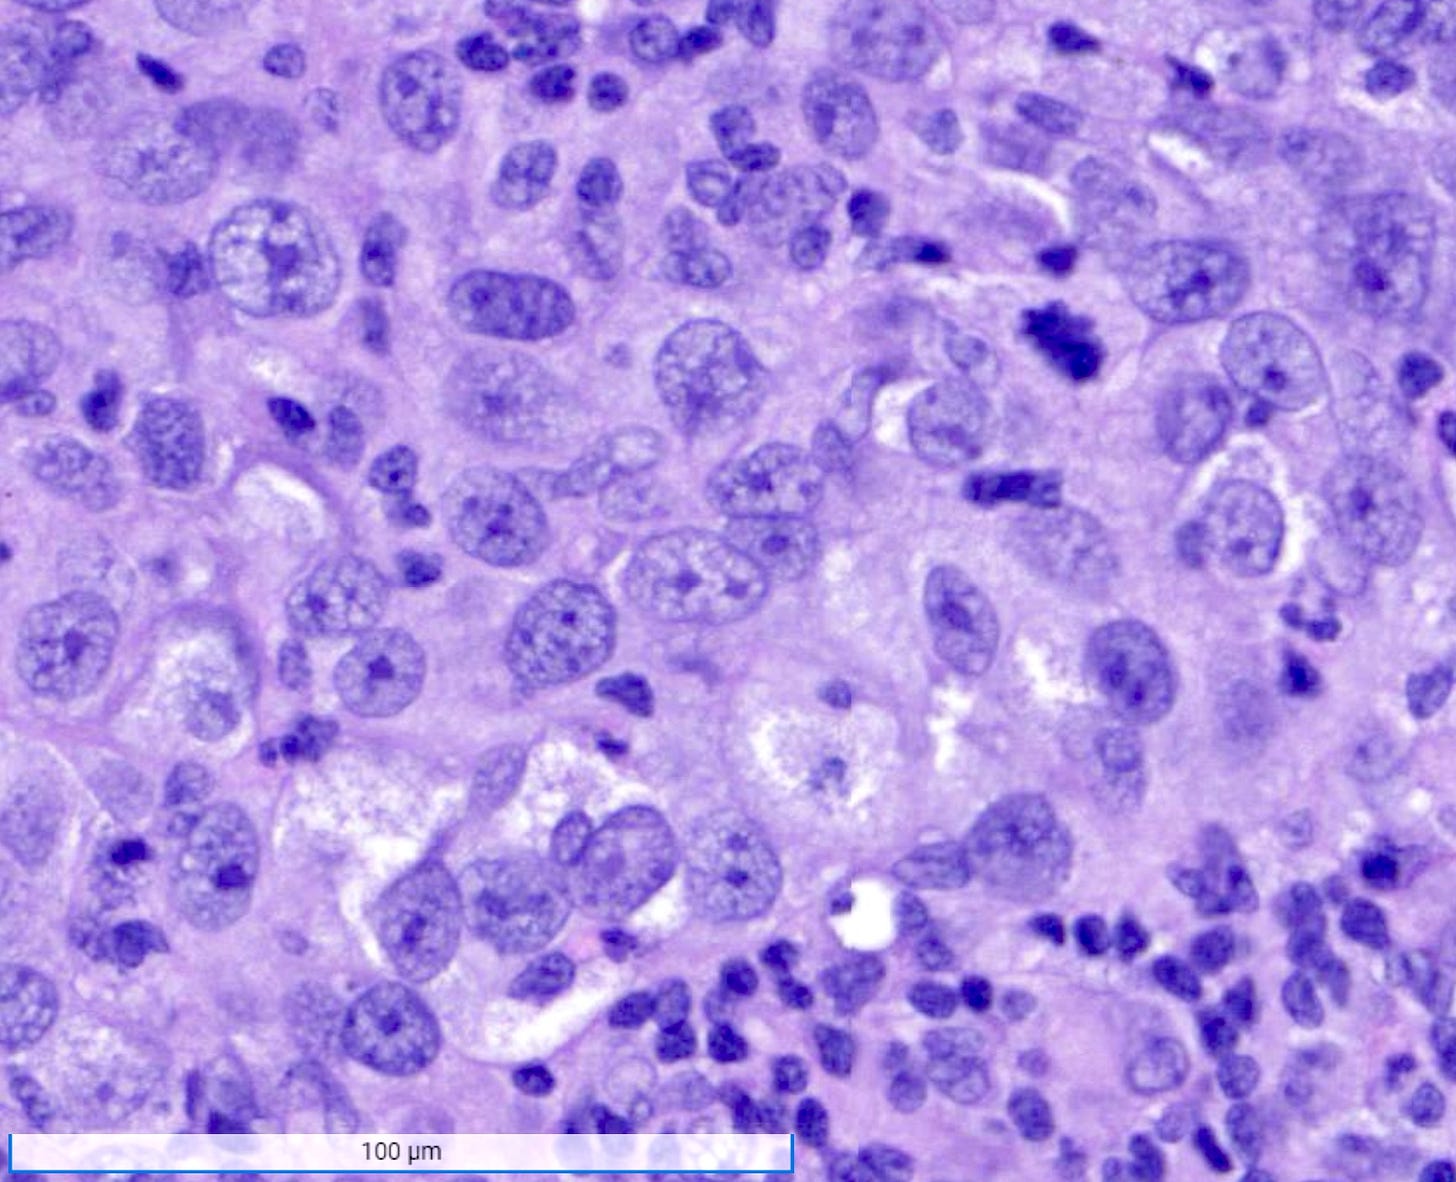

Microscopically, medullary carcinoma is composed of large, pleomorphic, high grade tumor cells arranged in broad syncytial sheets occupying at least 75% of the tumor area. The tumor cells have vesicular nuclei (i.e., large, pale staining with a central clearing) with prominent nucleoli and abundant eosinophilic cytoplasm. A prominent and dense lymphoplasmacytic infiltrate surrounds and often infiltrates the tumor, suggesting a vigorous host immune response. Mitotic figures are numerous and areas of necrosis may be present.

Medullary carcinoma - radiologic and microscopic images